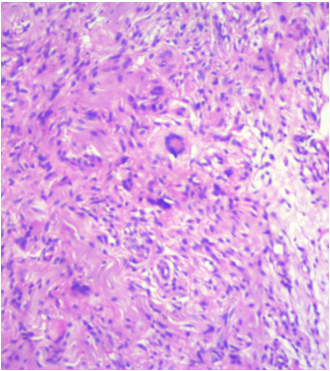

A 36-year-old male came with complaints of left upper eyelid swelling since 1 year. It was painless, not progressive and was treated as chalazion elsewhere but did not resolve. On examination, his visual acuity was normal with correction. Intraocular pressure and extraocular movements were normal. The left eyelid showed a localized swelling confined to the tarsal region with a slight yellowish tinge seen over the skin (Figure 1 [Fig. 1]). There was no erythema or tenderness. There was no evidence of pus, loss of eyelashes, changes in lid margin or prominent vessels. The palpebral conjunctiva was normal. We suspected it to be a sebaceous cyst. Excision biopsy was done and the sample was sent for histopathological examination which revealed a mixture of cells including polymorphs, plasma cells (Figure 2 [Fig. 2]), foamy macrophages (Figure 3 [Fig. 3]), and occasional Touton type of giant cells (Figure 4 [Fig. 4]). The inclusions in the macrophages turned out to be PAS positive suggestive of xanthogranuloma. The patient's systemic parameters were normal and on his review after 12 months he was doing well without any recurrence.

Figure 3: Histopathology showing foamy macrophages and plasma cells

Figure 6: Histopathology showing mononucleated foamy histiocytes (xanthoma cells), aggregates of lymphocytes, plasma cells, and Touton giant cells

Histopathologically, the xanthogranuloma is characterized by sheets of mononucleated foamy histiocytes (xanthoma cells) infiltrating the orbital tissue, accompanied by aggregates of lymphocytes, plasma cells, and Touton giant cells. These infiltrating xanthoma cells stain with Oil Red O [9]. However this stain only works in unfixed material (cryostat sections) but not in formalin fixed and paraffin embedded tissue.